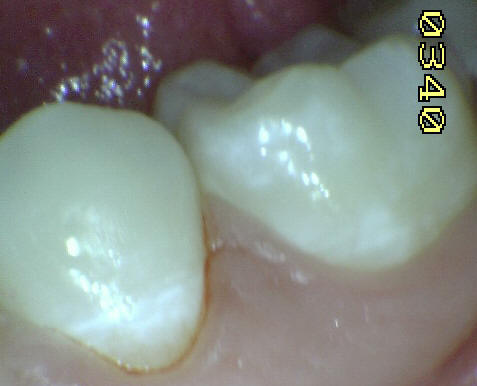

Casos clínicos de fluorosis leve.

Esmalte liso, traslucido y cristalino, con finas bandas horizontales de color blanquecino.